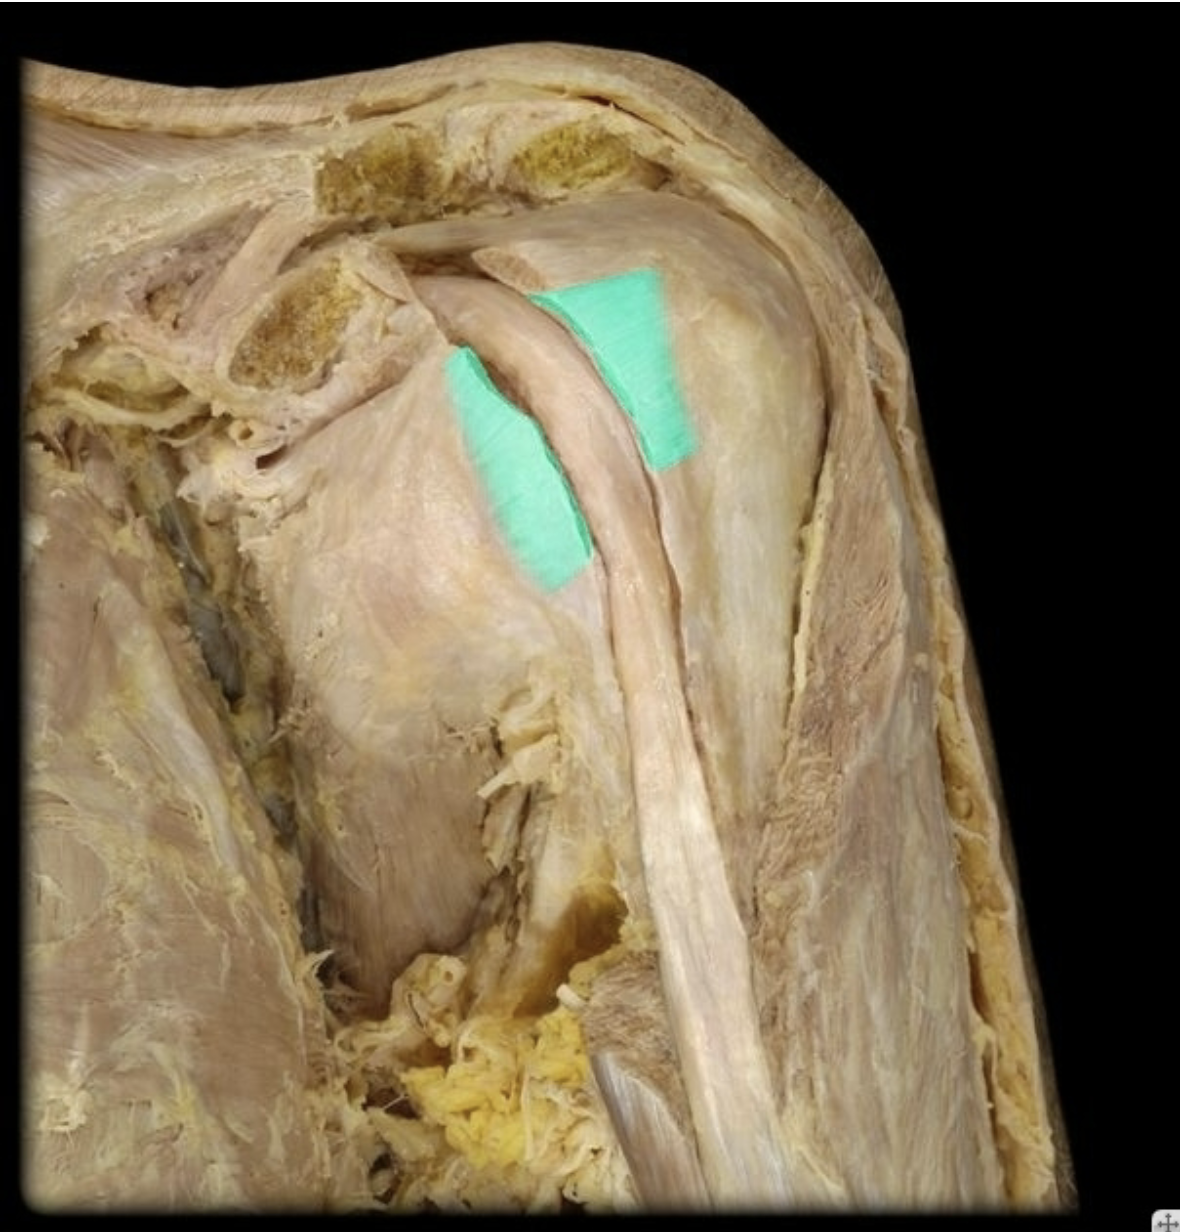

Musculotendinous (Rotator) Cuff

Glenoid Labrum

Glenohumeral ligament